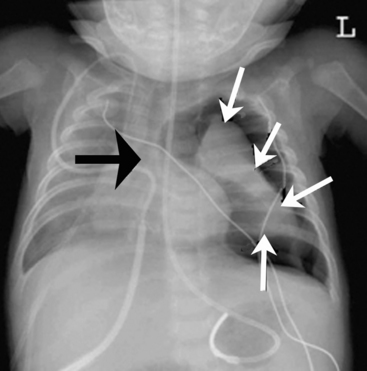

image

Fig. 10-3 Rib fractures. This chest radiograph of an 18-month-old girl was obtained as part of a series of films to evaluate for evidence of injuries caused by inflicted trauma. The child was admitted to the pediatric critical care unit with altered mental status, subdural hemorrhages, bilateral retinal hemorrhages, and areas of ecchymosis in various stages of healing. There are multiple healing rib fractures of different ages bilaterally, both medially and laterally (some indicated by the arrows) with no previous physician visits for trauma and no explanation for the injuries. Note the position of the tip of the nasogastric tube in the distal esophagus.